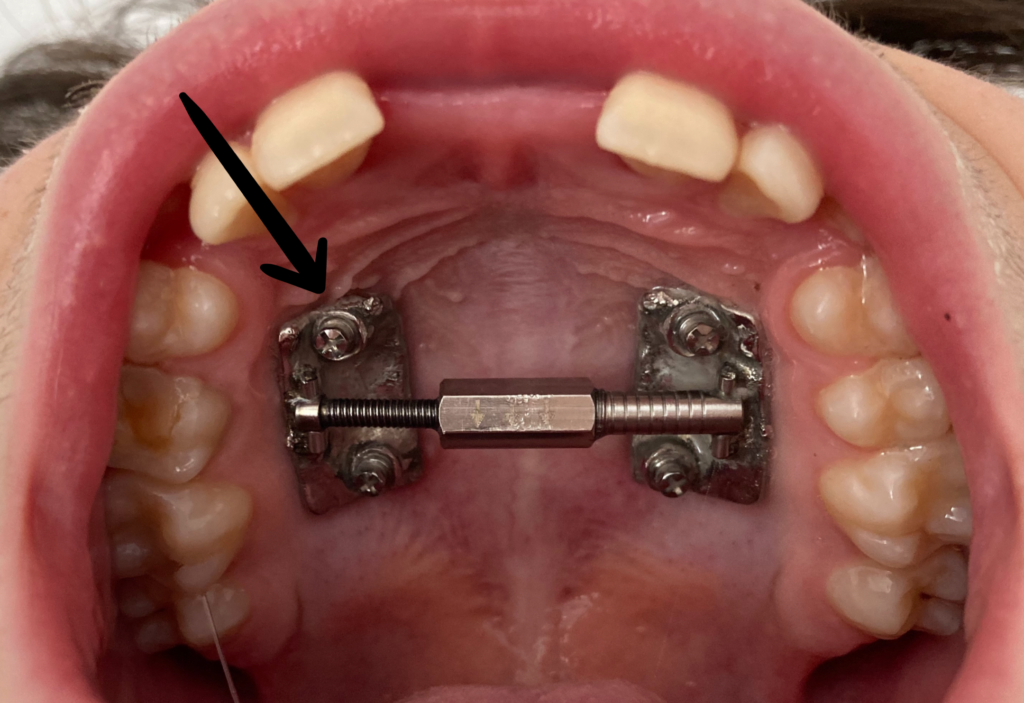

9. Microcargol afluixat, amb moviment o inflamació

En els tractaments amb aparells amb suport ossi, els cargols poden perdre força degut a restes de menjar que provoquen inflamació.

Si es dóna el cas, realitzeu els passos següents:

1. Contacteu amb la clínica Boca a Boca i agafeu hora amb la Dra. Villa. Els cargols són un tema quirúrgic i la Dra. Cubells no us pot ajudar en aquest sentit.

2. Higiene molt exhaustiva de la zona, especialment amb el fil dental i/o els raspallets interdentals. (Podeu mullar el fil o el raspallet amb clorhexidina).* Instruccions d’higiene

3. Apliqueu Gel de clorhexidina la llaga, després de cada raspallat i a demanda entre raspallats si cal.* (Producte complementari a les instruccions d’higiene; ells sols NO solucionaran la inflamació).

Microcargol anclat

Microcargol afluixat